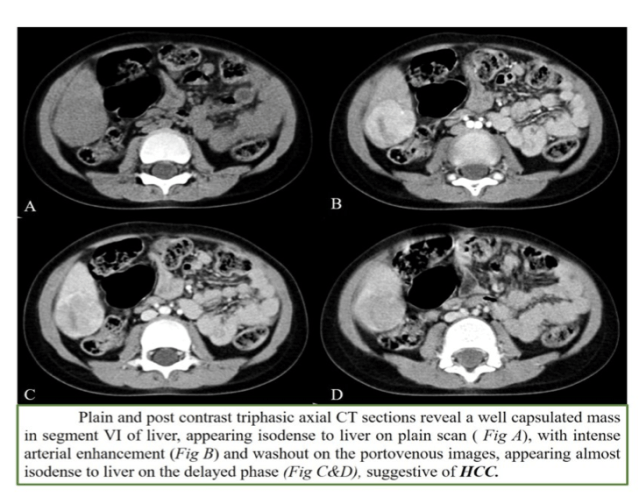

2. HCC

- Arterial phase enhancement with early washout (especially in cirrhosis-tyrosinemia etc)